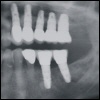

Grundsätzlich eignen sich Implantate in den unterschiedlichsten Fällen, angefangen vom Ersatz eines einzelnen Zahnes bis hin zum Ersatz aller Zähne im völlig zahnlosen Kiefer. Obwohl jeder Patientenfall individuell unterschiedlich ist, so lassen sich doch sehr gut anhand der verschiedene Lückengebisssituationen die Versorgungstypen einteilen.

Zahnloser Kiefer Der zahnlose Unterkiefer ist eine der ältesten ...